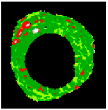

Figure 7 depicts the effectiveness of the KMPSO-mED model by segmenting the overlapping tissues in VH-IVUS images.

Figure 7.

Segmentation by KMPSO-mED: (a) overlapped tissue, and (b) segmented area.